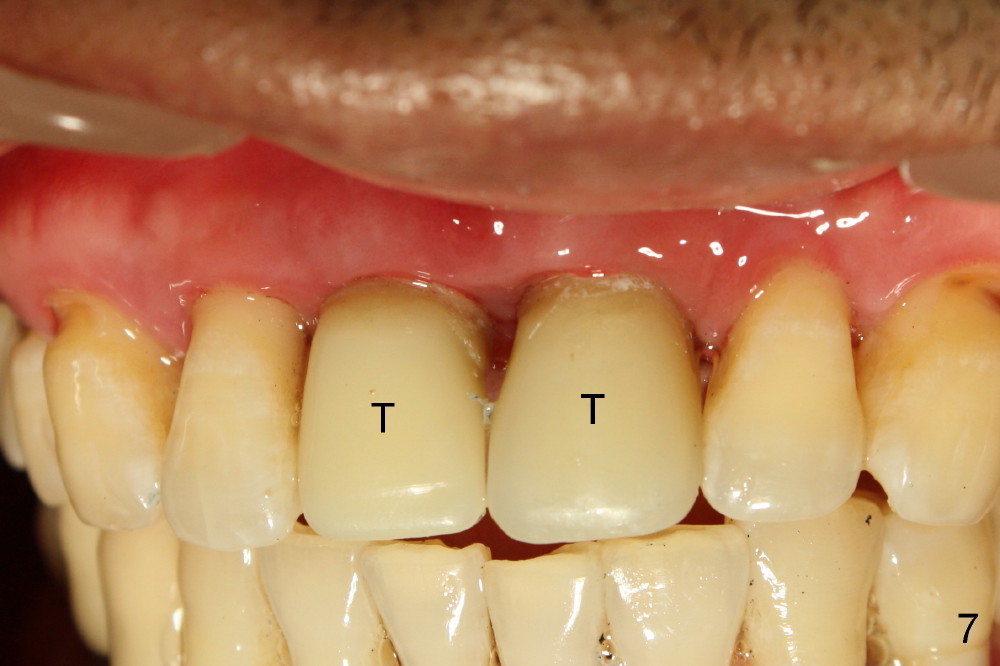

In fact two of 4.5x20 mm implants are placed immediately following extraction. Insertion torque is greater than 60 Ncm, partially because of apparent engagement of the implants into the nasal floor (cortical bone; Fig.9). Following placement of 3.5x5 mm abutments, immediate provisionals are fabricated (Fig.7,8).